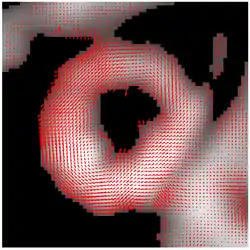

The result of HARP tracking of one frame of cardiac MRI is shown in the figure. It is obtained by calculating both motions from horizontal direction and vertical direction, resulting in a 2D vector field showing the motion of every material point on the myocardium at this time frame.